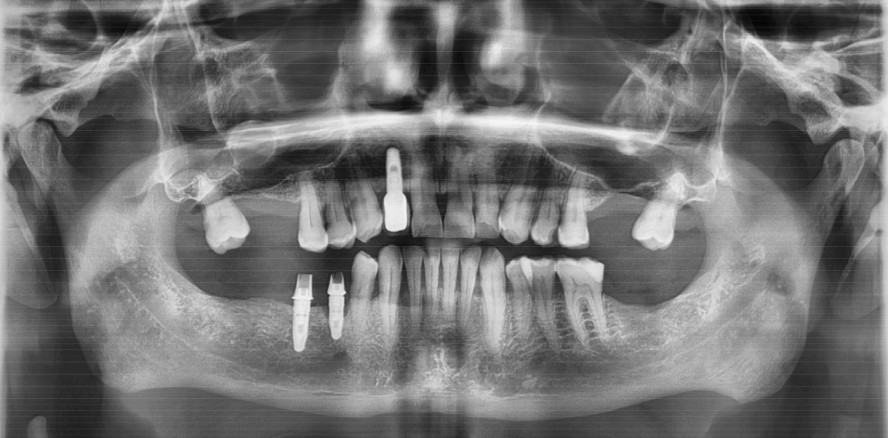

Einschlusskriterien waren, dass es Oberkieferfront-Einzelimplantate waren, mindestens seit fünf Jahren mit einer festsitzenden Suprakonstruktion versorgt und der betrachtete UIT-Zeitraum ab Untersuchung bei fünf Jahren lag. Die Definition der Periimplantitis in dieser Studie war ab Blutung nach Sondierung, Lockerung, Schwellung oder einer Taschentiefe ab 2 mm gemessen ab Implantatschulter.